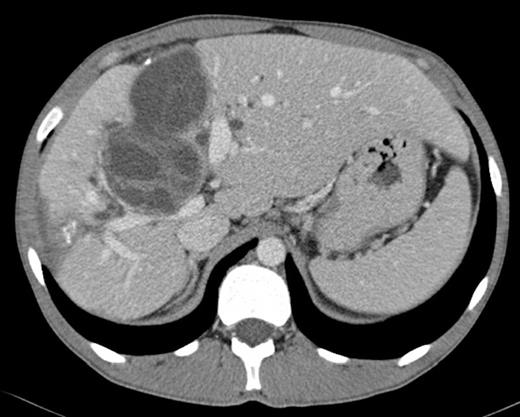

Surgical exploration confirmed the numerous peritoneal hydatid cysts and identified more lesions in the larger omentum (ranging from 3-12 cm) (Fig. 3). They were all resected, and a splenectomy was performed to remove completely the hilum cyst (Fig.4). Hydatid disease of the liver was massive, except in segments 1, 2 and 3. A cyst developing in segment 7 (7 cm) invaded the diaphragm and another voluminous cyst of 12 cm occupied the entire segment 8. A cyst of 8 cm in segments 4 and 5 involved the hepatic confluence, with destruction of the right hepatic duct and promoting a major biliary fistula with the left hepatic duct, confirmed by intra-operative transcystic cholangiography. The left hepatic duct near the hilar plate was included in the pericystic wall near segment 3. This cyst was chemically inactivated using iodopovidone (20 minutes), evacuated and followed by a thorough exploration of the cavity, which showed multiple biliary fistulae from the right sectorial hepatic ducts and a large defect in the left hepatic duct (Fig. 5). An extended right hepatectomy (segments 4 – 8), partial resection of the diaphragm and partial resection of the left hepatic duct including the fistula was performed. Reconstruction of biliary continuity was assured by a hepaticocholedocostomy, over a T-tube (Fig. 6). Confirmation of sectorial left hepatic ducts patency was done by intra-operative cholangiography.